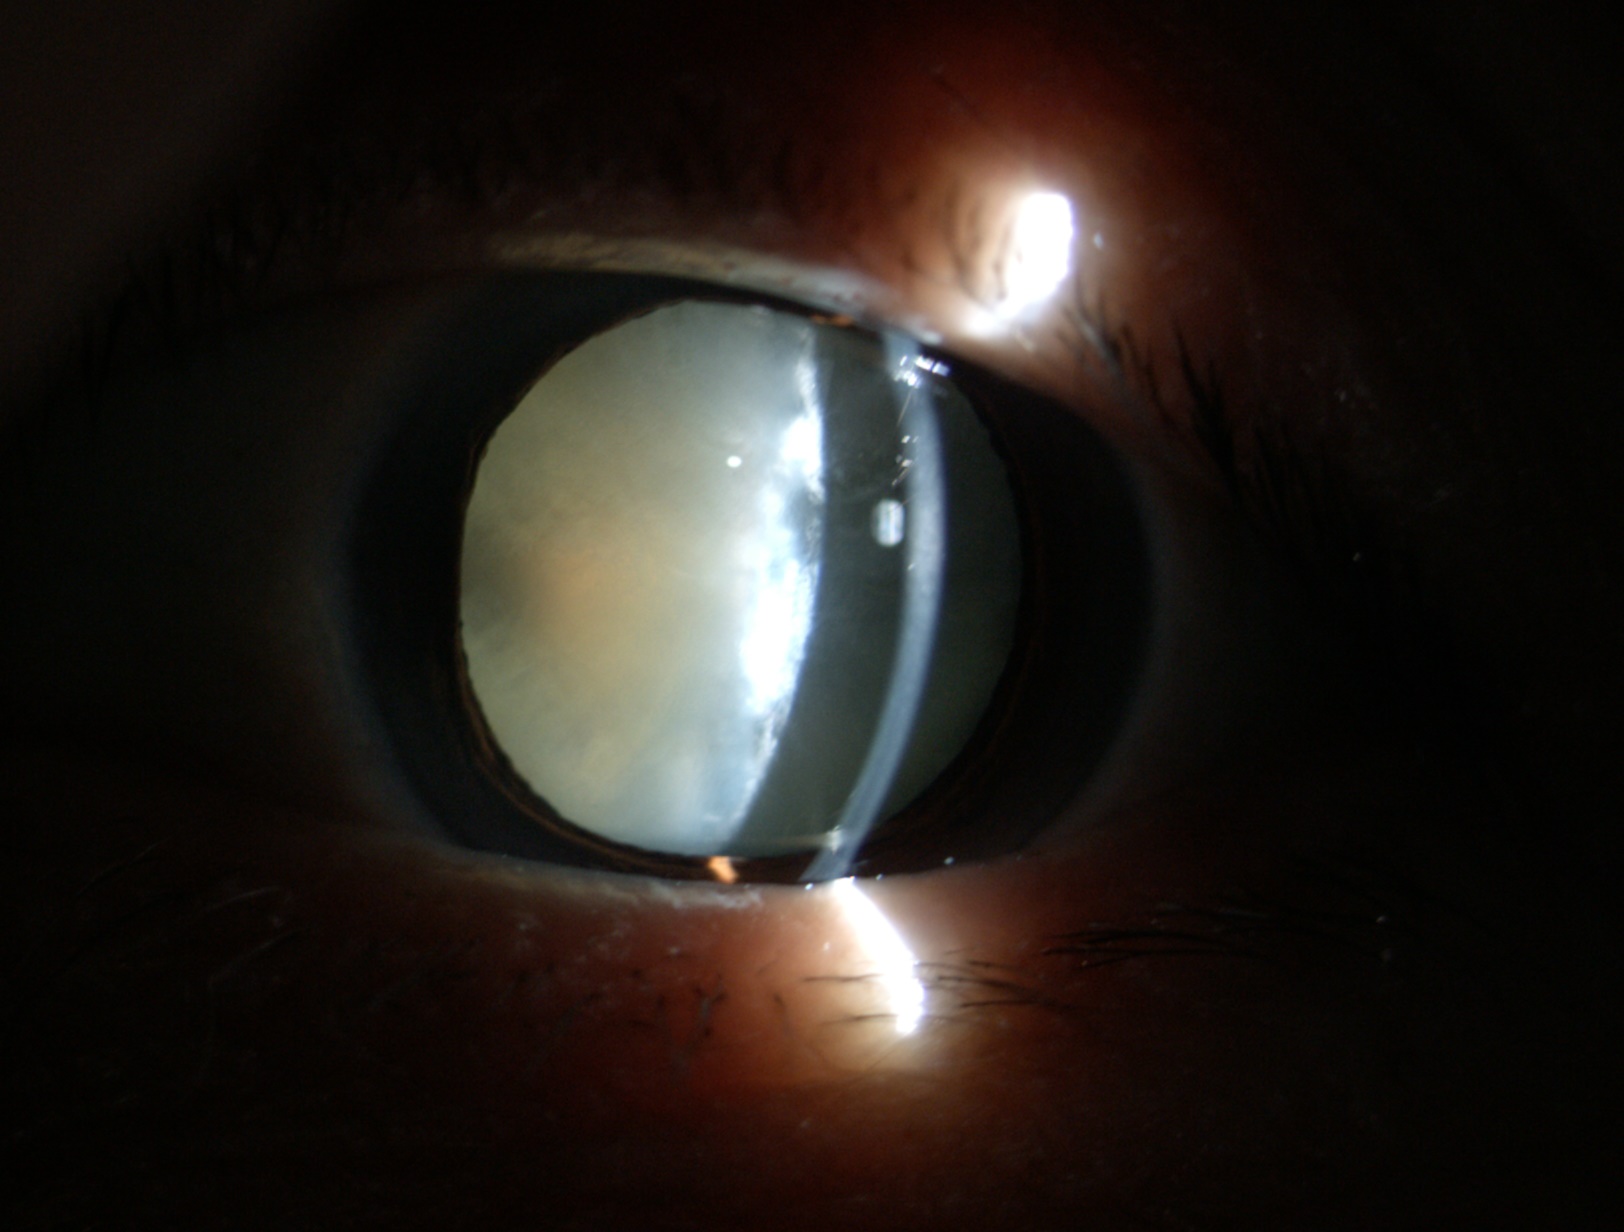

老年性白內(nèi)障

夏季強(qiáng)烈的陽光通常使瞳孔變小,此時(shí)往往視力下降更明顯,適合手術(shù)者更應(yīng)當(dāng)機(jī)立斷。